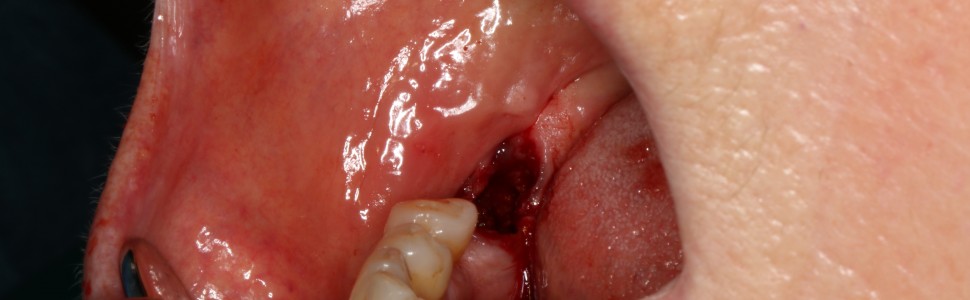

W znieczuleniu nasiękowym i przewodowym z zastosowaniem dentocaine 4% (podano 4 ampułki) usunięto minimalnie inwazyjnie ząb 47. Następnie wykonano płat śluzówkowo-okostnowy i dotarto do jamy torbieli. Usunięto ząb 48 oraz wyłuszczono zmianę, którą następnie oddano do badania histopatologicznego. Ranę zaopatrzono szwami 4-0 oraz opatrunkiem chirurgicznym (ryc. 2).

Ryc. 2. Zdjęcia śródzabiegowe: a) okolica operowana; b) stan po usunięciu zęba 47; c) wykonanie płata śluzówkowo-okostnowego, widoczny ząb 48; d) wyłuszczenie zmiany, obecna gruba torebka łącznotkankowa; e) loża pozabiegowa; f) usunięte zęby 47 i 48; g) stan pozabiegowy; h) aspirat ze zmiany (grudzień 2020).